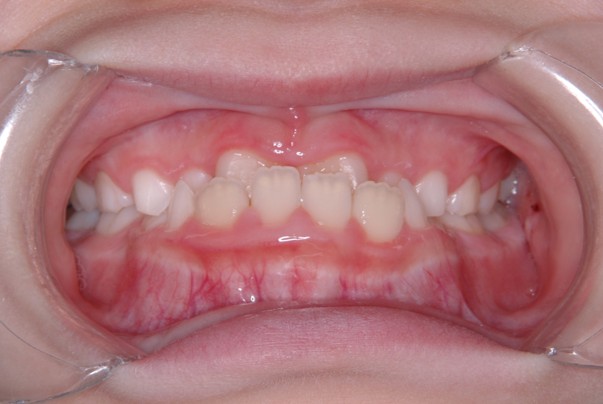

歯並びや口元の美しさへの関心が高まり、早い段階から矯正治療を始める方が増えています。それに伴い、価格の安さを前面に出した矯正ブランドや、マウスピース型矯正装置のみを扱う歯科医院も増えてきました。しかし、これらは軽度から中等度の歯並び改善を中心としており、「見た目だけを整える」治療に留まってしまうケースも少なくありません。

歯並びは口元だけでなく、お顔全体の骨格や筋肉バランスを考えて整えることが大切です。

当院では、横顔のEラインや口元と目元・頬の調和など、顔全体のバランスにこだわり、自然な表情に馴染む美しい歯並びを追求しています。

患者様一人ひとりの骨格や顔立ちに合わせたオーダーメイドの治療で、自信の持てる笑顔づくりをサポートします。

症例

矯正歯科専門の歯科医師が専門的な知識と確かな実績を

もとに患者様にあった最適な治療プランをご提案します。